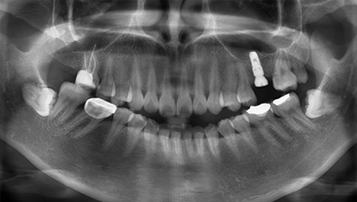

진단 및 치료 계획

파노라마, X-ray, 3D CT 등으로 상태를 면밀하게 진단 후 치료계획을 세웁니다.

임플란트 식립

잇몸뼈가 형성되면 임플란트를 식립합니다.

W Dental Clinic Before & After

치료 전후사진

Before

After